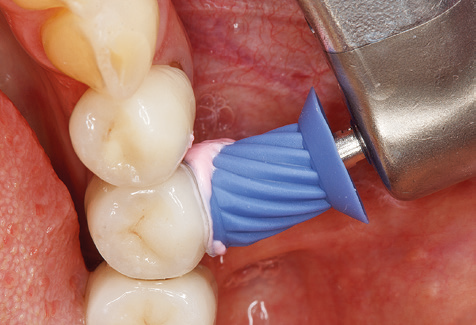

Fig. 4: Flexible probes with millimetre markings are recommended for the probing of dental implants (e.g. Colorvue Kit PCV11KIT6, Hu­Friedy). – Fig. 5a and b: A straight working tip (1P, W&H Dentalwerk Bürmoos GmbH) is a suitable instrument for use on all natural teeth. – Fig. 6: Curved working tips (3Pr/3Pl, W&H Dentalwerk Bürmoos GmbH) lend themselves to the processing of difficult-to-reach areas of the tooth and root surfaces (e.g. furcations). – Fig. 7: The tapered, hexagonal implant cleaning tip (1I, W&H Dentalwerk Bürmoos GmbH) permits atraumatic and efficient cleaning of the crown and abutment surfaces. – Fig. 8: Titanium and carbon curettes are suitable instruments for the manual cleaning of the implant surfaces.

Following machine cleaning of the tooth and implant surfaces, the surfaces of the natural teeth are cleaned manually using standard hand instruments. When performing manual cleaning, particular attention must be given to maintaining the correct angle of application, appropriate sharpness, good support and working with the curette from apical to coronal. Either titanium or carbon curettes should be used for post-cleaning of the implant structures (Fig. 8). In addition to the use of ultrasonic devices, power jet devices can also be used in conservative dentistry. However, it must be taken into consideration that these procedures are not suitable for removing hard deposits and thus they cannot replace the use of hand instruments and ultrasonic instruments completely. In all cases, cleaning is followed by mechanical polishing of the accessible tooth and implant surfaces with polishing cups and polishing compounds (Fig. 9).